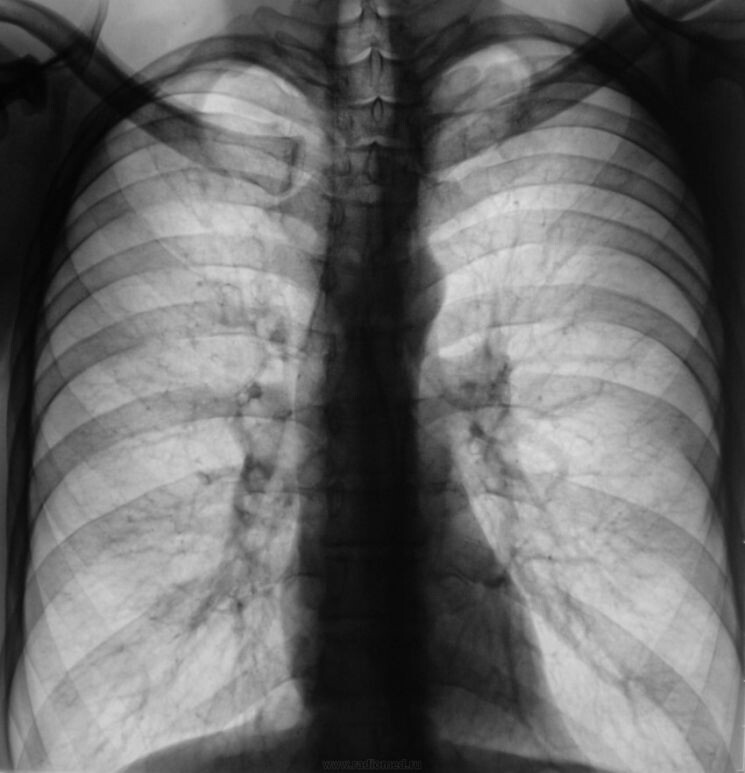

Взяли анализы, провели необходимые мед.обследования и опираясь на рентген снимки подтвердили ранее поставленный диагноз.

Самое абсурдно было то, что все анализы пришли отрицательные, клинических подтверждений не было, диагноз был поставлен по рентген снимкам.